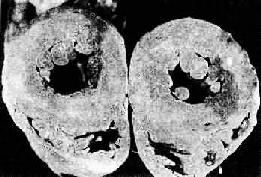

6.縮窄性心包炎及限制型心肌病縮窄性心包炎為心包膜纖維化、僵硬及鈣化束縛心臟,使四個心腔舒張期充盈受限。限制型心肌病則是心內膜、心肌纖維化、或心肌異常組織沉積,使室壁僵硬度增加,心臟舒張功能障礙以舒張中晚期顯著。兩者血流動力學改變相似,均為心室充盈受阻,心室舒張末壓力升高,壓力曲線呈舒張早期下陷,後期呈高原波、肺動脈壓及肺動脈阻力增高,心排血量減少。